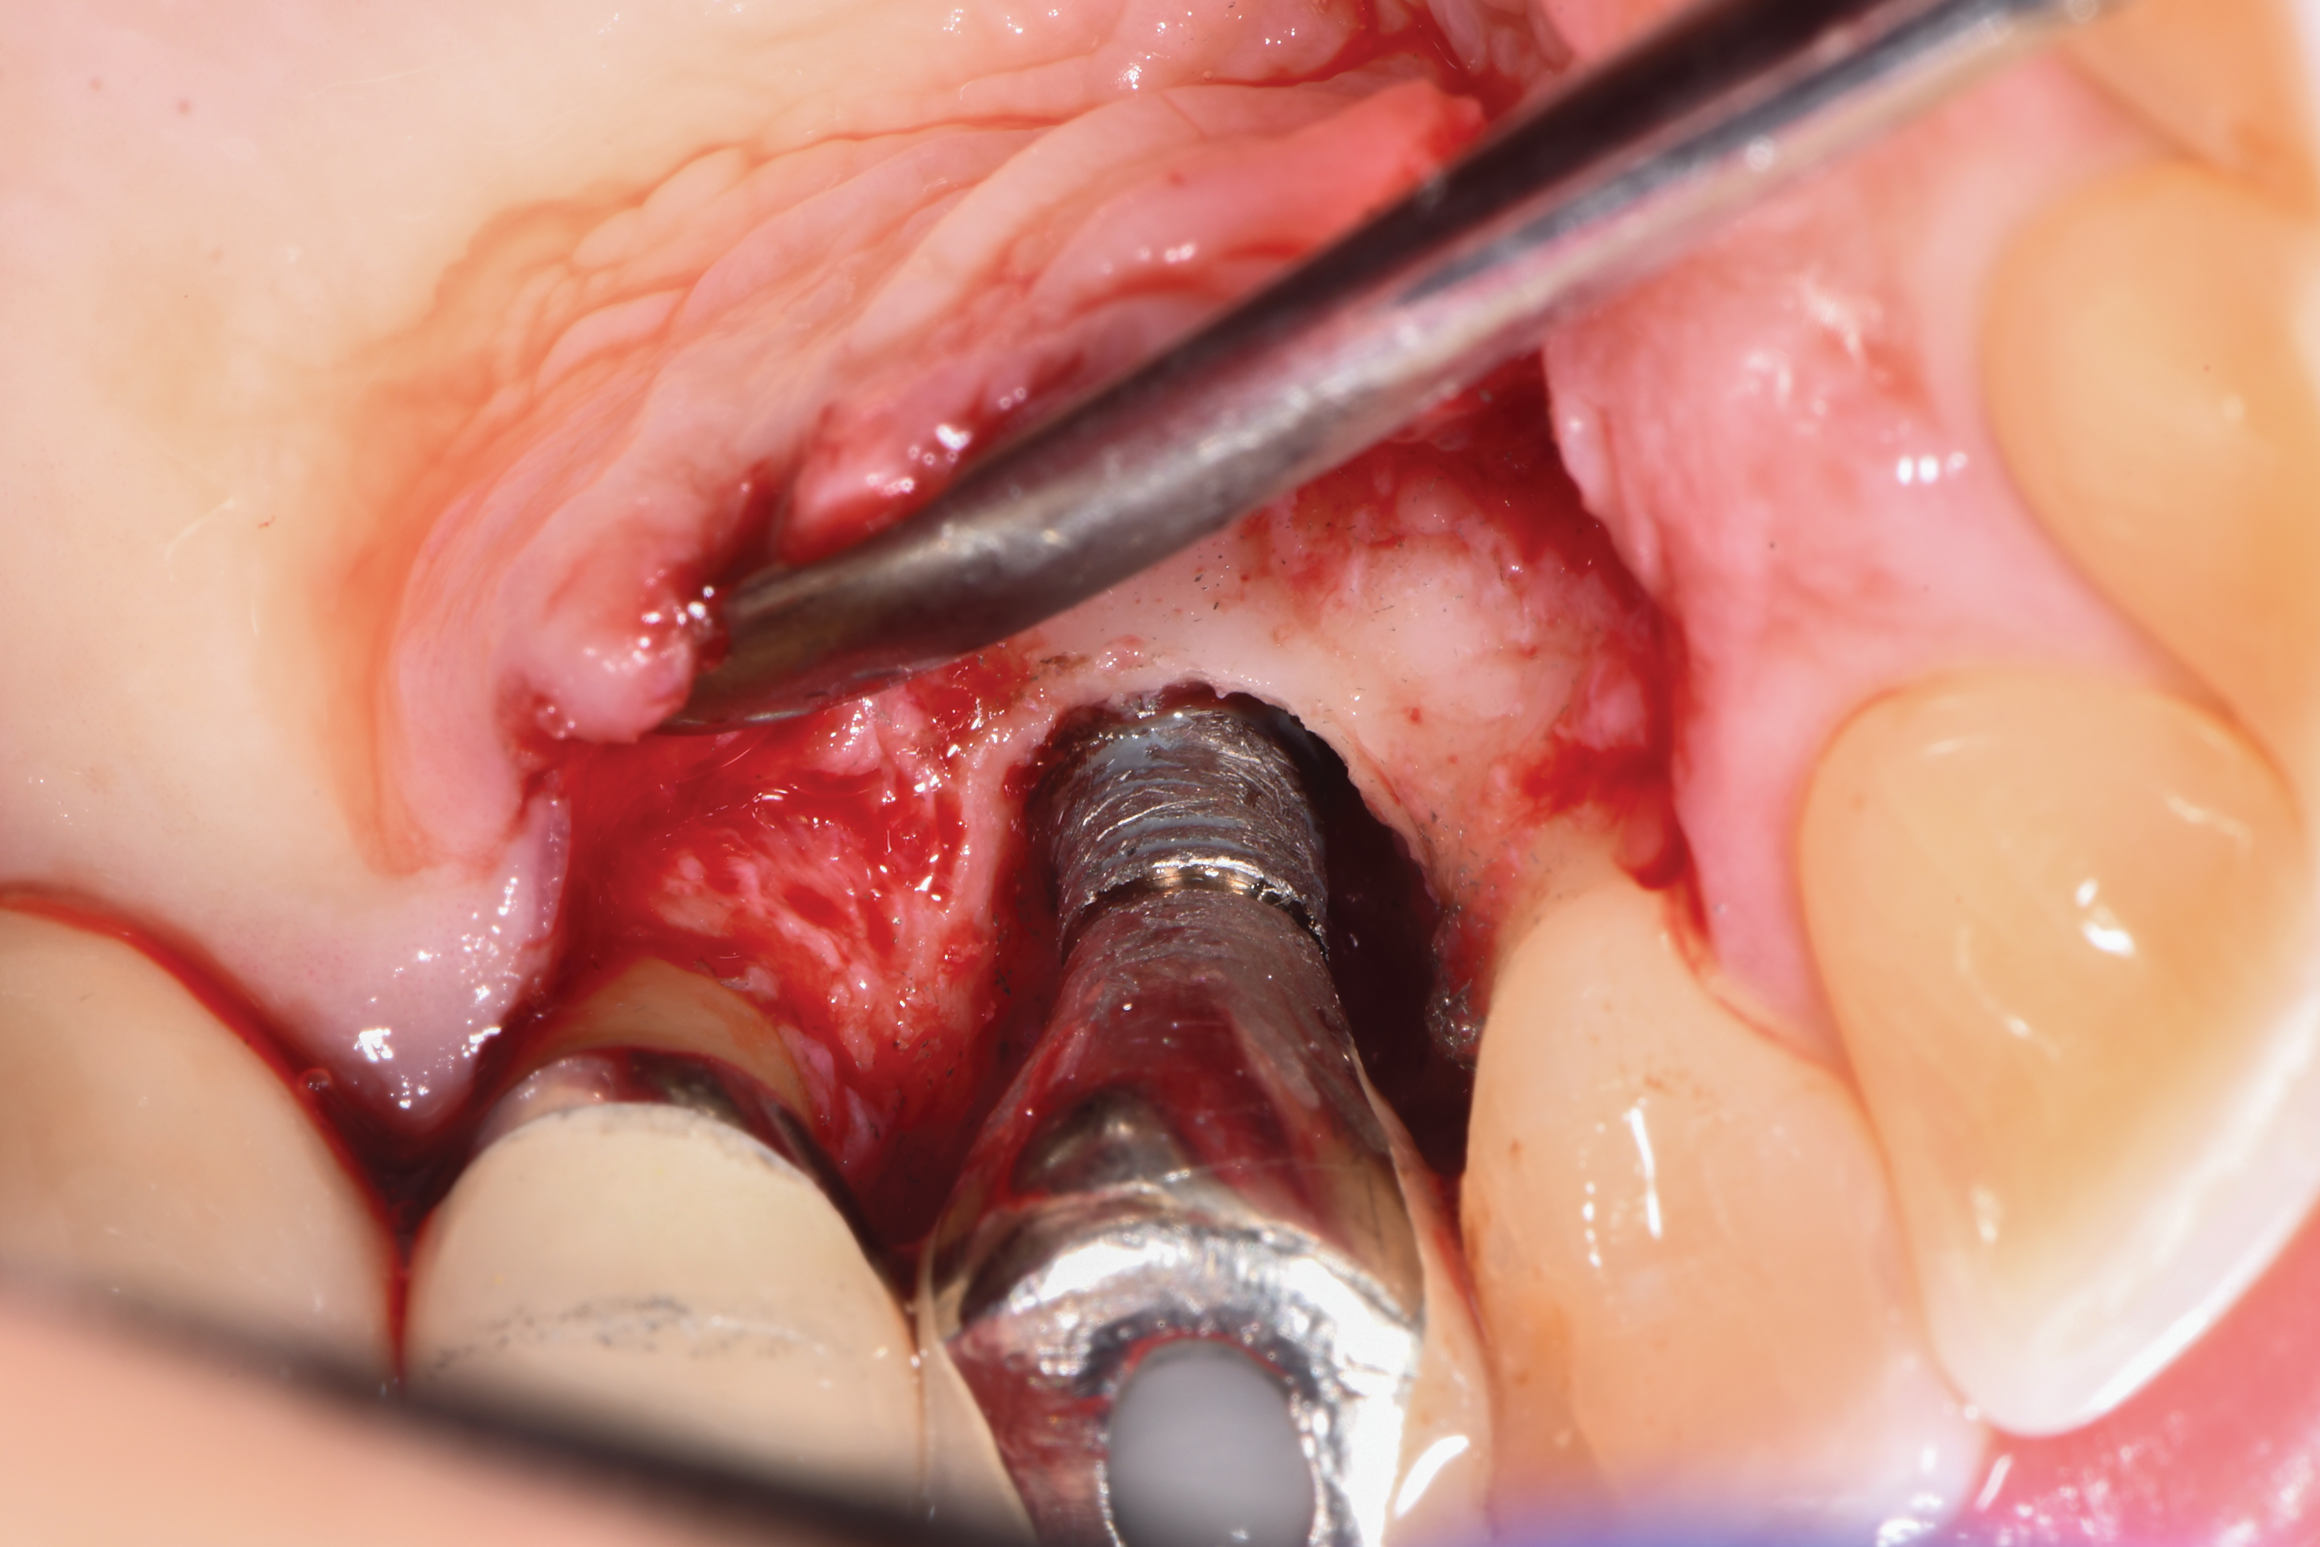

After local anesthesia was administered, full-thickness flaps were elevated from the buccal and lingual aspects of tooth No. 27 to the distobuccal and lingual aspects of tooth No. 31. Removal of granulomatous tissue from the implant site allowed visualization of a combination lesion with two walls at the distal and two to three walls at the mesial with a circumferential configuration on the lingual (Figure 12). The surface was initially treated with a 50% solution of citric acid for 30 seconds, which was burnished on with cotton pellets followed by thorough rinsing with sterile saline. This was followed by implantoplasty using 12-fluted followed by 30-fluted surgical-length finishing burs that provided access to the base of the defect. Because the crown was cemented, which obviated access, a matte-like surface could not be achieved; thus, the goal was to reduce the threads and remove the outer affected surface to expose fresh titanium (Figure 13). At this stage, the implant was wiped again with citric acid and rinsed with sterile saline.

Fig 12. The lesion was visualized upon flap reflection. A three- to two-wall lesion on the mesial wrapped to the lingual, while the distal had a two-wall lesion that also extended to the lingual as a moat.

Figure 12